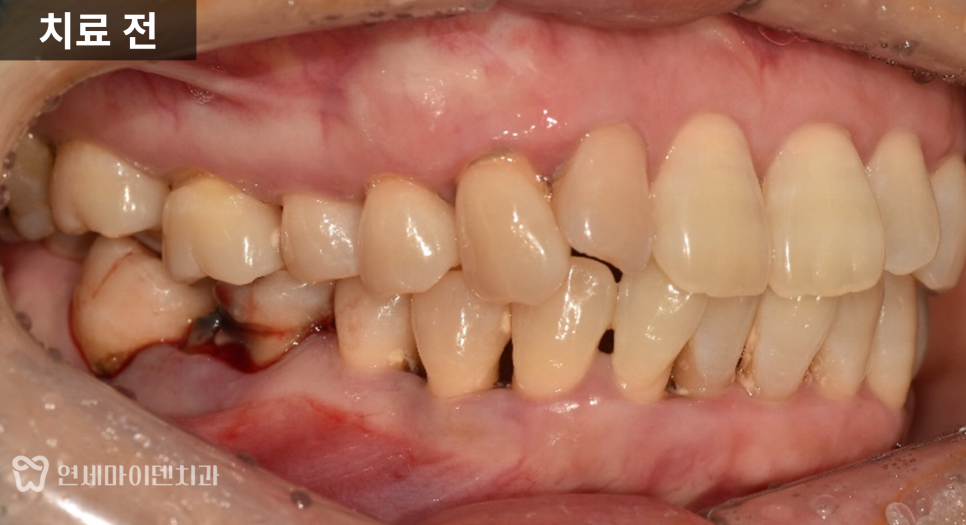

잇몸이 자주 붓고 피가 나며,

어금니가 흔들려 식사가 어려운 상태에서

내원하시는 경우가 적지 않습니다.

이번 케이스는

잇몸이 자주 붓고 출혈이 있으며,

고름이 반복되는 상태였습니다.

아래 어금니 한 부위

이미 크게 파절되어 있었고,

주변 잇몸에는

치석과 염증이 많이 축적되어 있었습니다.